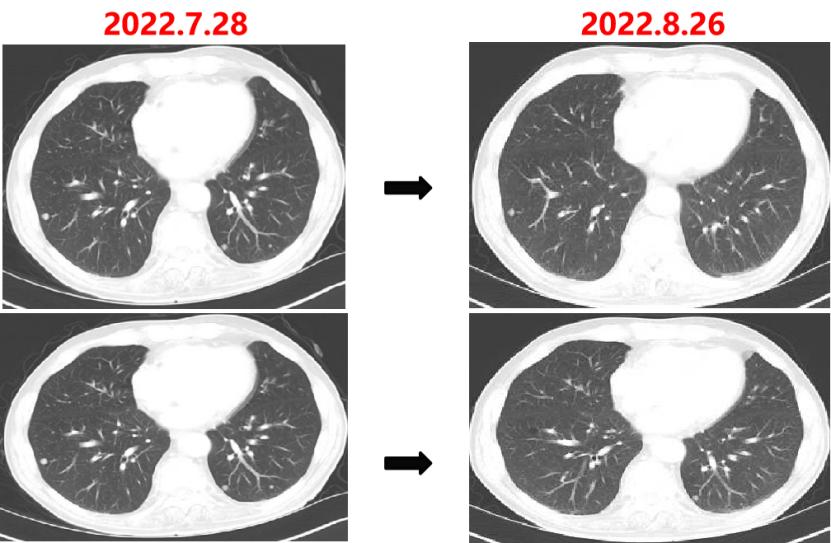

2022-07-27至今

给予贝伐珠单抗联合TAS-102治疗期间复查CT评估SD,胃肠道反应不重,骨髓抑制Ⅰ度,耐受性尚可。